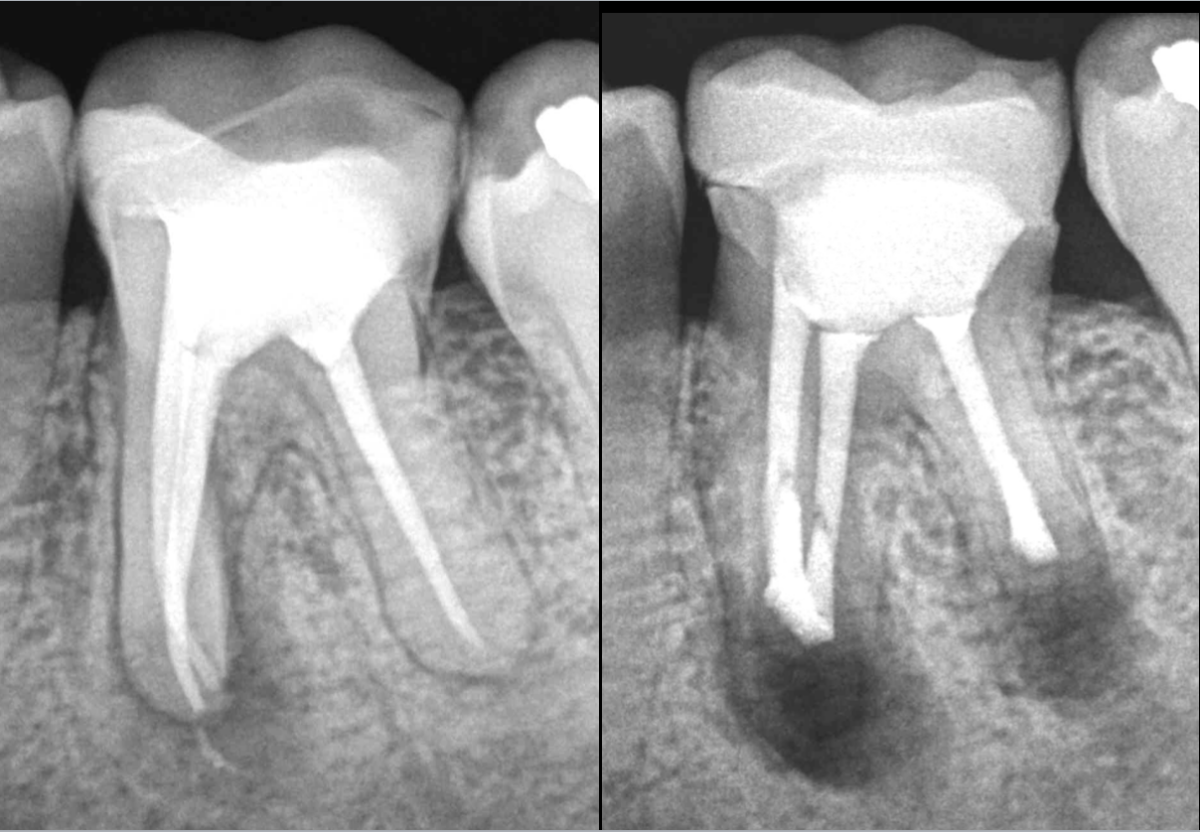

𝐏𝐮𝐥𝐩𝐞 𝐩𝐫𝐞́𝐜𝐞́𝐝𝐞𝐦𝐦𝐞𝐧𝐭 𝐭𝐫𝐚𝐢𝐭𝐞́𝐞, 𝐩𝐚𝐫𝐨𝐝𝐨𝐧𝐭𝐢𝐭𝐞 𝐚𝐩𝐢𝐜𝐚𝐥𝐞 𝐬𝐲𝐦𝐩𝐭𝐨𝐦𝐚𝐭𝐢𝐪𝐮𝐞

𝐏𝐫𝐨𝐭𝐡𝐞̀𝐬𝐞 𝐚𝐝𝐚𝐩𝐭𝐞́𝐞, 𝐭𝐫𝐚𝐢𝐭𝐞𝐦𝐞𝐧𝐭 𝐜𝐨𝐫𝐫𝐞𝐜𝐭.

➡️ Microchirurgie endodontique des racines M et D.

Est-ce que l’isthme est toujours cliniquement visible entre les canaux MV et ML ❓